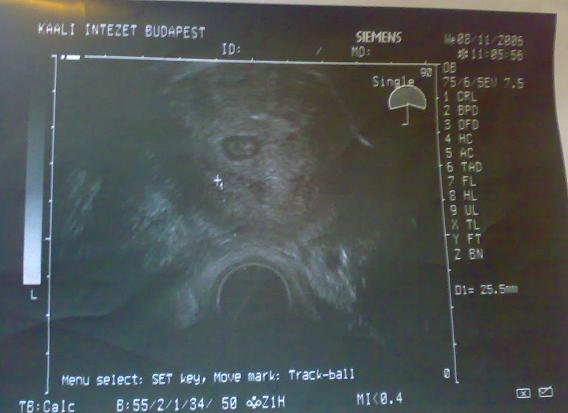

Az jutott eszembe, hogy ahogy repül az idő, nem soká Botiról is hasonló képet fogok mutogatni!